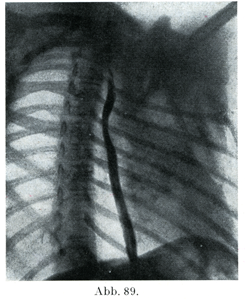

局所解剖:食道はまず気管と脊柱(椎前筋膜が被っている)とのあいだにあり,気管とは強固な結合組織により,脊柱とは疎な結合組織により連なっていて,最初のうちはその前方にある気管の方が幅がひろいので,食道はそのかげに全くかくれている.しかしまもなく食道は左の方に偏してきて,そのため胸腔に入る前に,食道の左縁が気管の左縁と一致するようになり,さらに下方では気管の左縁のところに見えてくる.ついで食道は左の気管麦と交叉する.この高さから下では食道はだんだんと脊柱から離れる(図89).そして胸大動脈の前方で長くひきのばされた1つのラセンをえがくのである.胸大動脈の初まりの部は食道の左側に接しているが,それより下になるとこの動脈は脊柱と食道のあいだに入りこむ.そして食道が横隔膜を通り抜けるときは食道が大動脈より左方に離れているが(図88),これは胃の噴門に移行するためである.気管分岐部より下方では食道は長い距離にわたって心膜のうしろにあり,そのさいまず食道神経叢にとりまかれるが,さらに下方になると迷走神経の前幹と後幹Truncus ventralis, dorsalis n. vagiに伴なわれている.食道はその経過のおよそ中央のところで右側で或る距離だけ右側の胸膜で被われている.頚部では甲状腺の外側葉が食道の側縁に少しの範囲ながら接している.

[図89]若い男(およそ20才)の食道レントゲン像 第1斜径で腹背方向に照射.(Pratje, Z. Anat. Entw.,81. Bd.,1926)